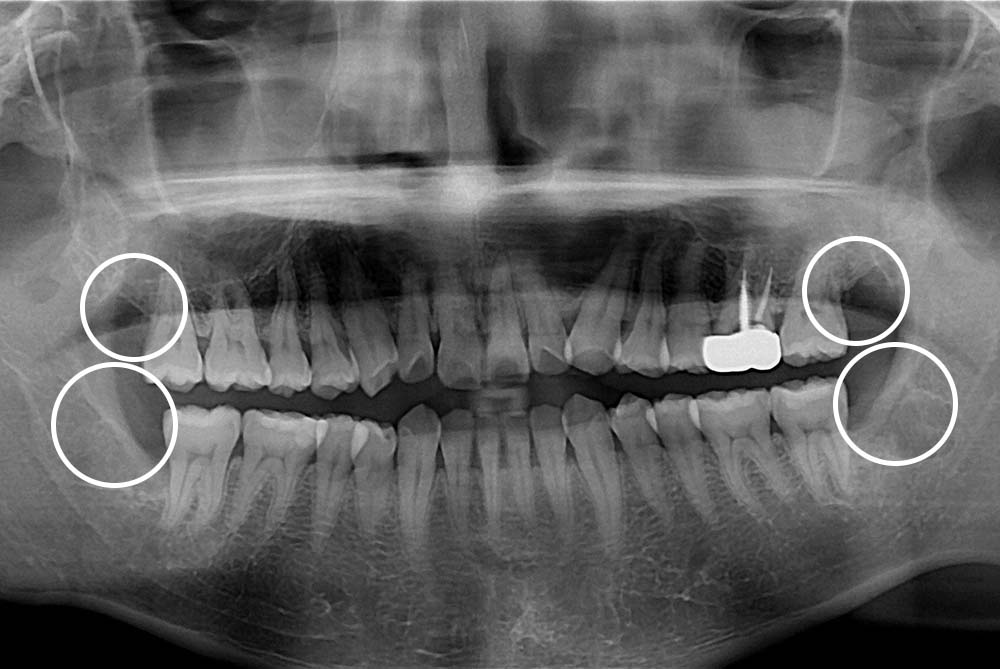

[사랑니] 매복 사랑니 발치

치료전 : 2019-03-18